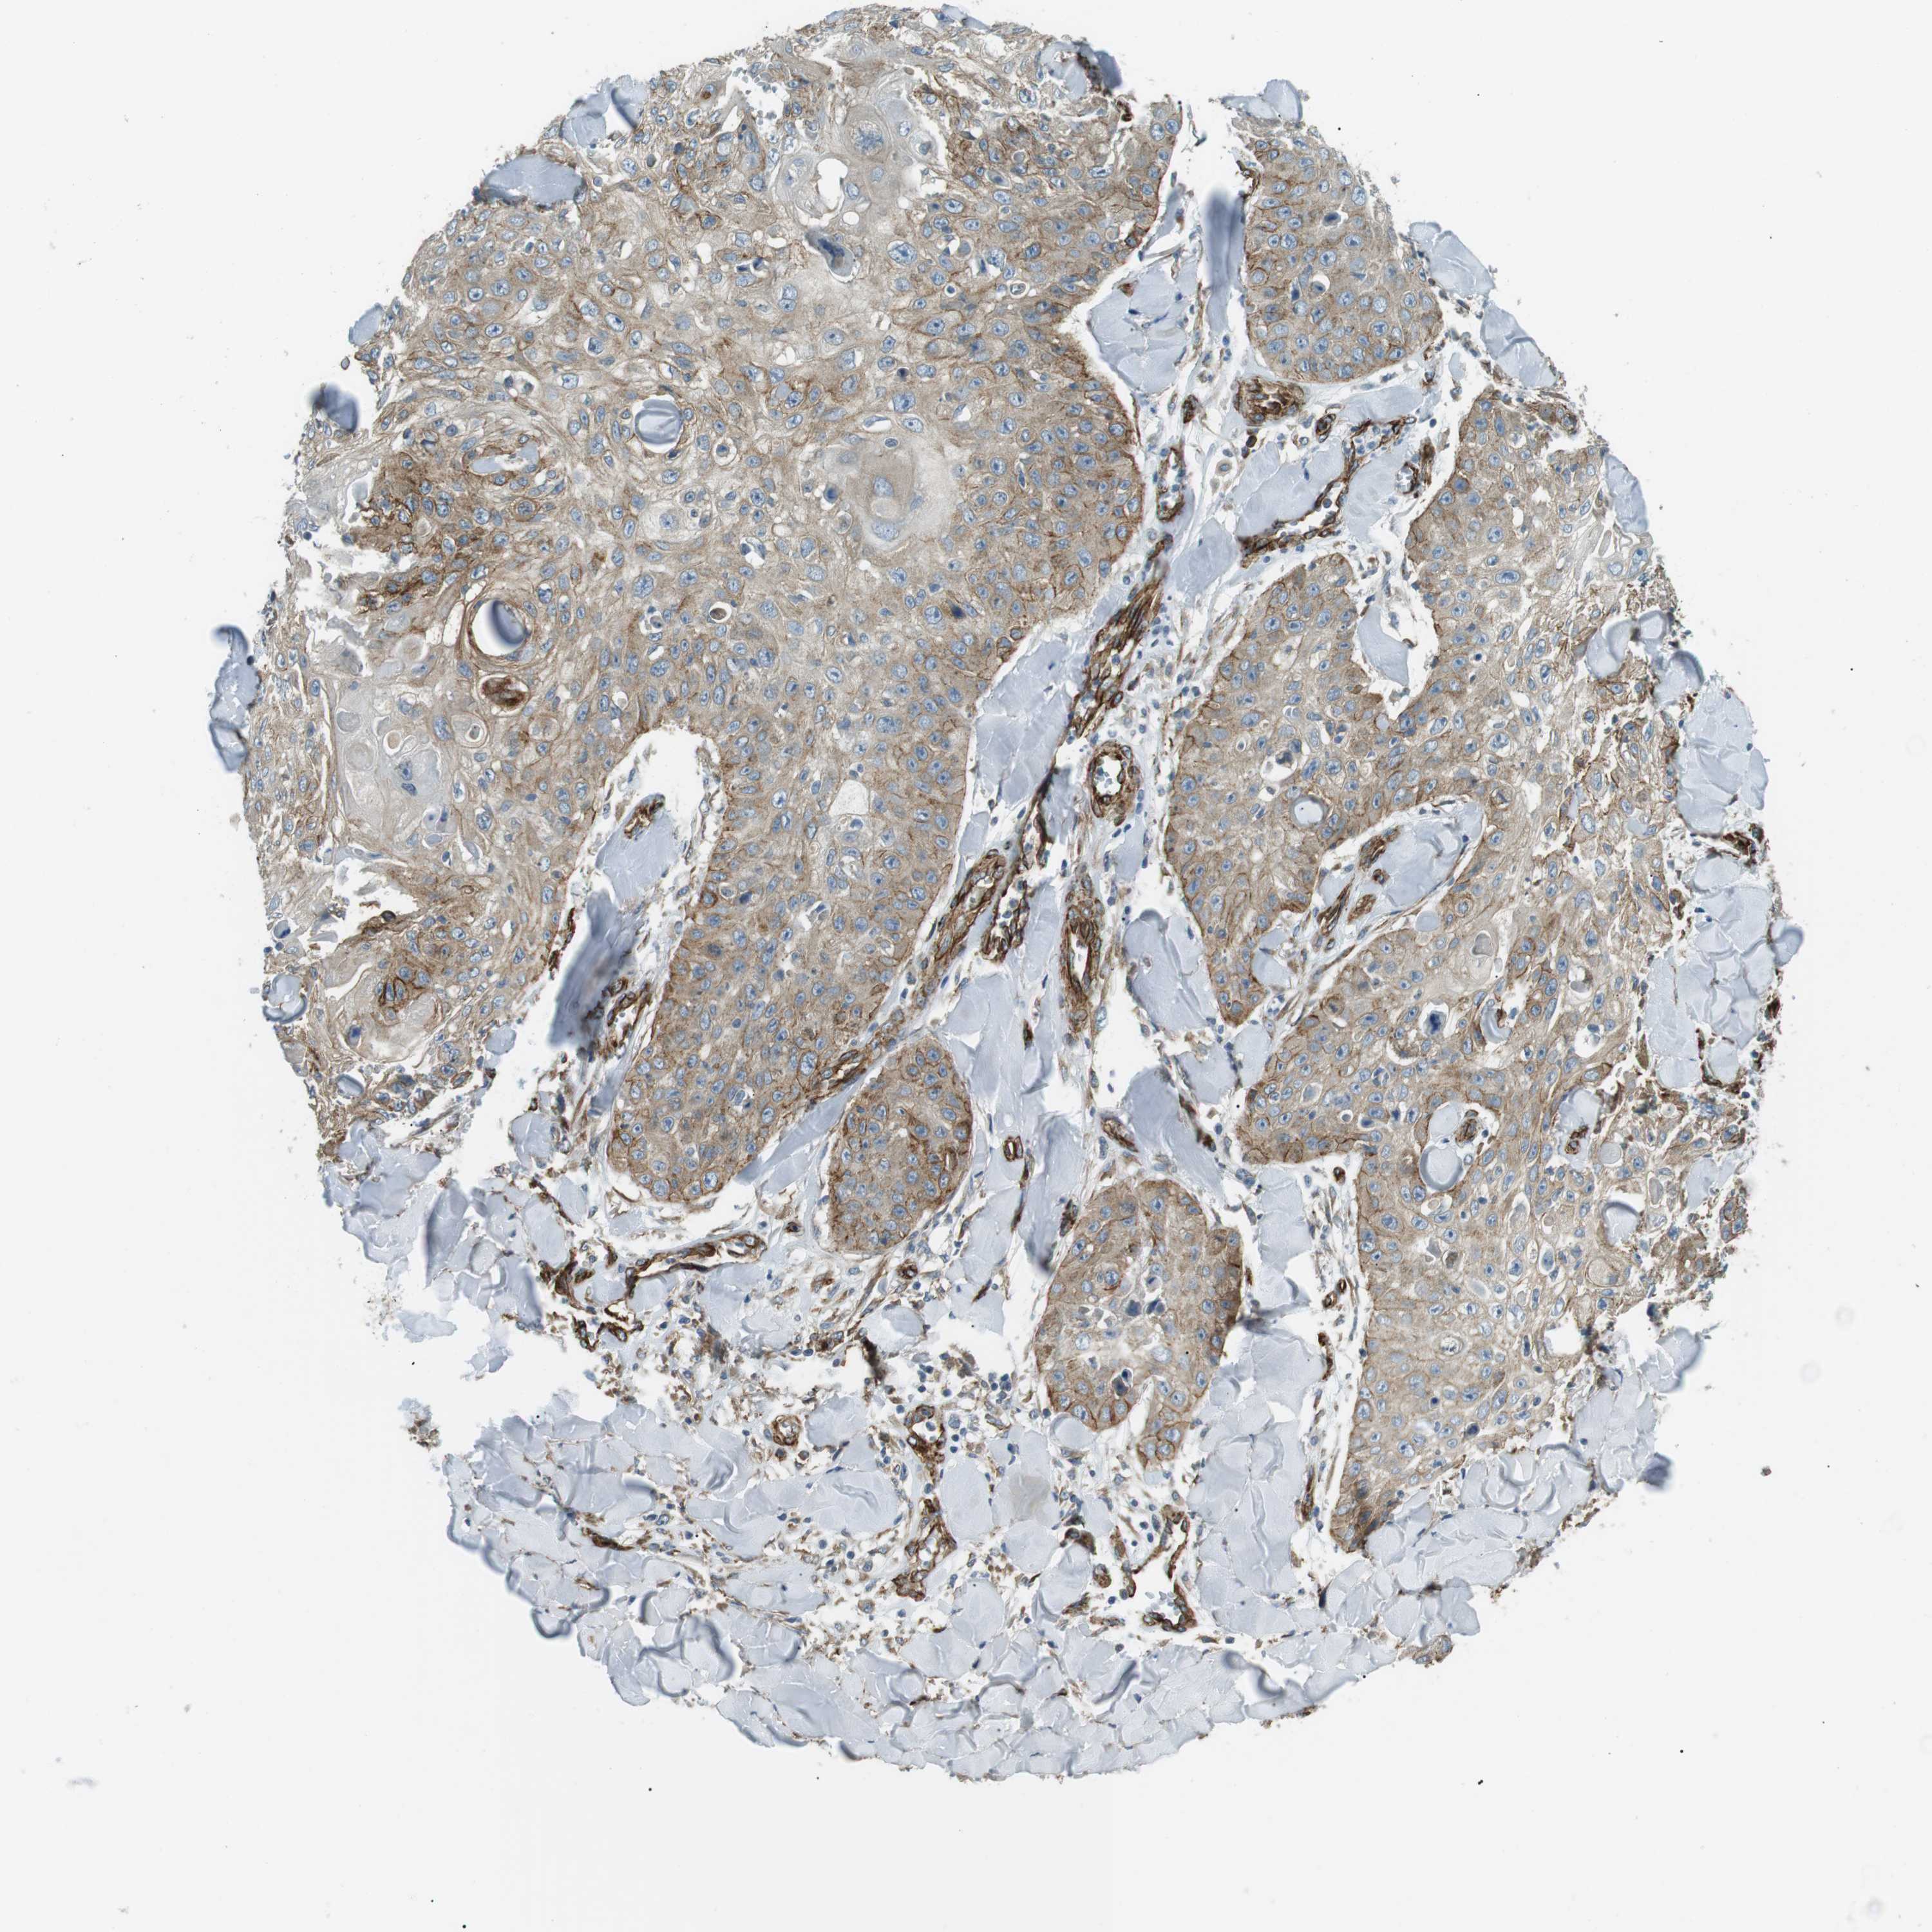

SKIN CANCER - Protein expressioni

A mouse-over function shows sample information and annotation data. Click on an image to view it in a full screen mode. Samples can be filtered based on level of antibody staining by selecting one or several of the following categories: high, medium, low and not detected. The assay and annotation is described here.

Antibody staining in the annotated cell types in the current human tissue is reported as not detected, low, medium, or high, based on conventional immunohistochemistry profiling in selected tissues. This score is based on the combination of the staining intensity and fraction of stained cells.

Each image is clickable and will lead to virtual microscopy that enables deeper exploration of all samples and also displays staining intensity scores, fraction scores and subcellular localization as well as patient and tissue information for each sample.

Antibody HPA015988

Staining

High

Medium

Low

Not detected

Intensity

Strong

Moderate

Weak

Negative

Quantity

>75%

75%-25%

<25%

None

Location

Nuclear

Cytoplasmic/membranous

Cytoplasmic/membranous,nuclear

Squamous cell carcinoma in situ, NOS

Squamous cell carcinoma, NOS

Basal cell carcinoma

Adnexal tumor, benign